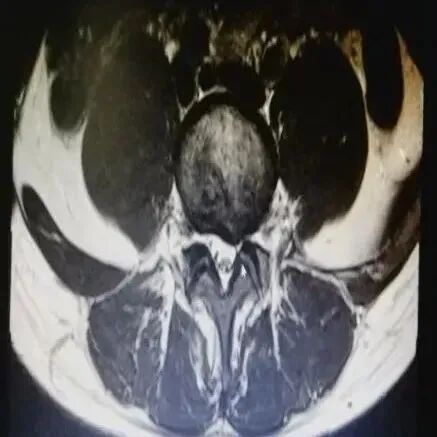

病史摘要:患者郑某,女性,49岁,饭店老板,三年前因腰背部疼痛诊断为腰肌劳损,进行相关治疗;一年前因腰痛就诊,MR诊断为:腰椎间盘膨出,腰背部筋膜炎;给予腰椎牵引及相关理疗,疼痛好转。后因腰背痛及左下肢麻木,肌力减退,日常生活活动受限,睡眠质量差及步行障碍于康复门诊就诊,MRI诊断:L5/S1椎间盘左中央旁型突出。当时结合其临床表现及相关影像资料给予其进行病情及功能状况评估,排除激光磁治疗禁忌。其主要功能障碍有:腰背部酸痛、左下肢麻木、左下肢肌力减退、日常生活受限、睡眠质量差、情绪焦躁,针对患者的功能情况,制定相应治疗目标及方案。

疼痛仪怎么回事快来看!激光磁场理疗仪疼痛的克星!_https://www.jmylbn.com_新闻资讯_第7张

该患者激光磁治疗部位:腰部、左臀部、左小腿痛点。治疗强度:65%。治疗频率:3-30Hz。治疗时间:25分钟。qd。

经过10次积极的激光磁康复治疗后,患者病情平稳,功能障碍显著改善,腰痛症状消失,下肢麻木症状明显缓解,生活质量及睡眠改善。